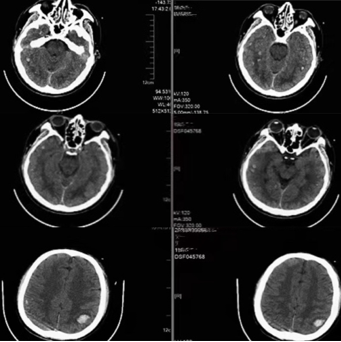

此时,入院检查结果也陆续回报。CT显示颅内多发出血点、肺部感染、肝脏密度减低,血检结果提示肝肾功能衰竭、高血氨、横纹肌溶解、心功能不全、凝血功能障碍、电解质紊乱,但脑脊液相关结果并不支持颅内感染。综合患者的临床表现、实验室检查及影像,以脏器功能衰竭、凝血功能障碍、微血管病变为主要特征。考虑到小马有野外工作史,因此怀疑有流行性出血热的可能,经过标本检测,结果回报阴性,进而排除这一可能。小马近期一直在接受抗结核药物治疗,转而考虑药物中毒的可能性。但治疗期间小马一直定期复查肝肾功能,不久前的结果还提示正常,而此次发病后肝功能迅速恶化,甚至达到了爆发性肝衰竭的诊断标准,并伴有横纹肌溶解,很有可能涉及其他更多的因素。随后医生再次详细地向家属了解情况,得知小马在发病前2天曾大量食用网上购买的生蚝,结合发病的表现和检查的结果,考虑食物中毒的可能性极大。

(头颅CT提示颅内弥漫性多发性出血)